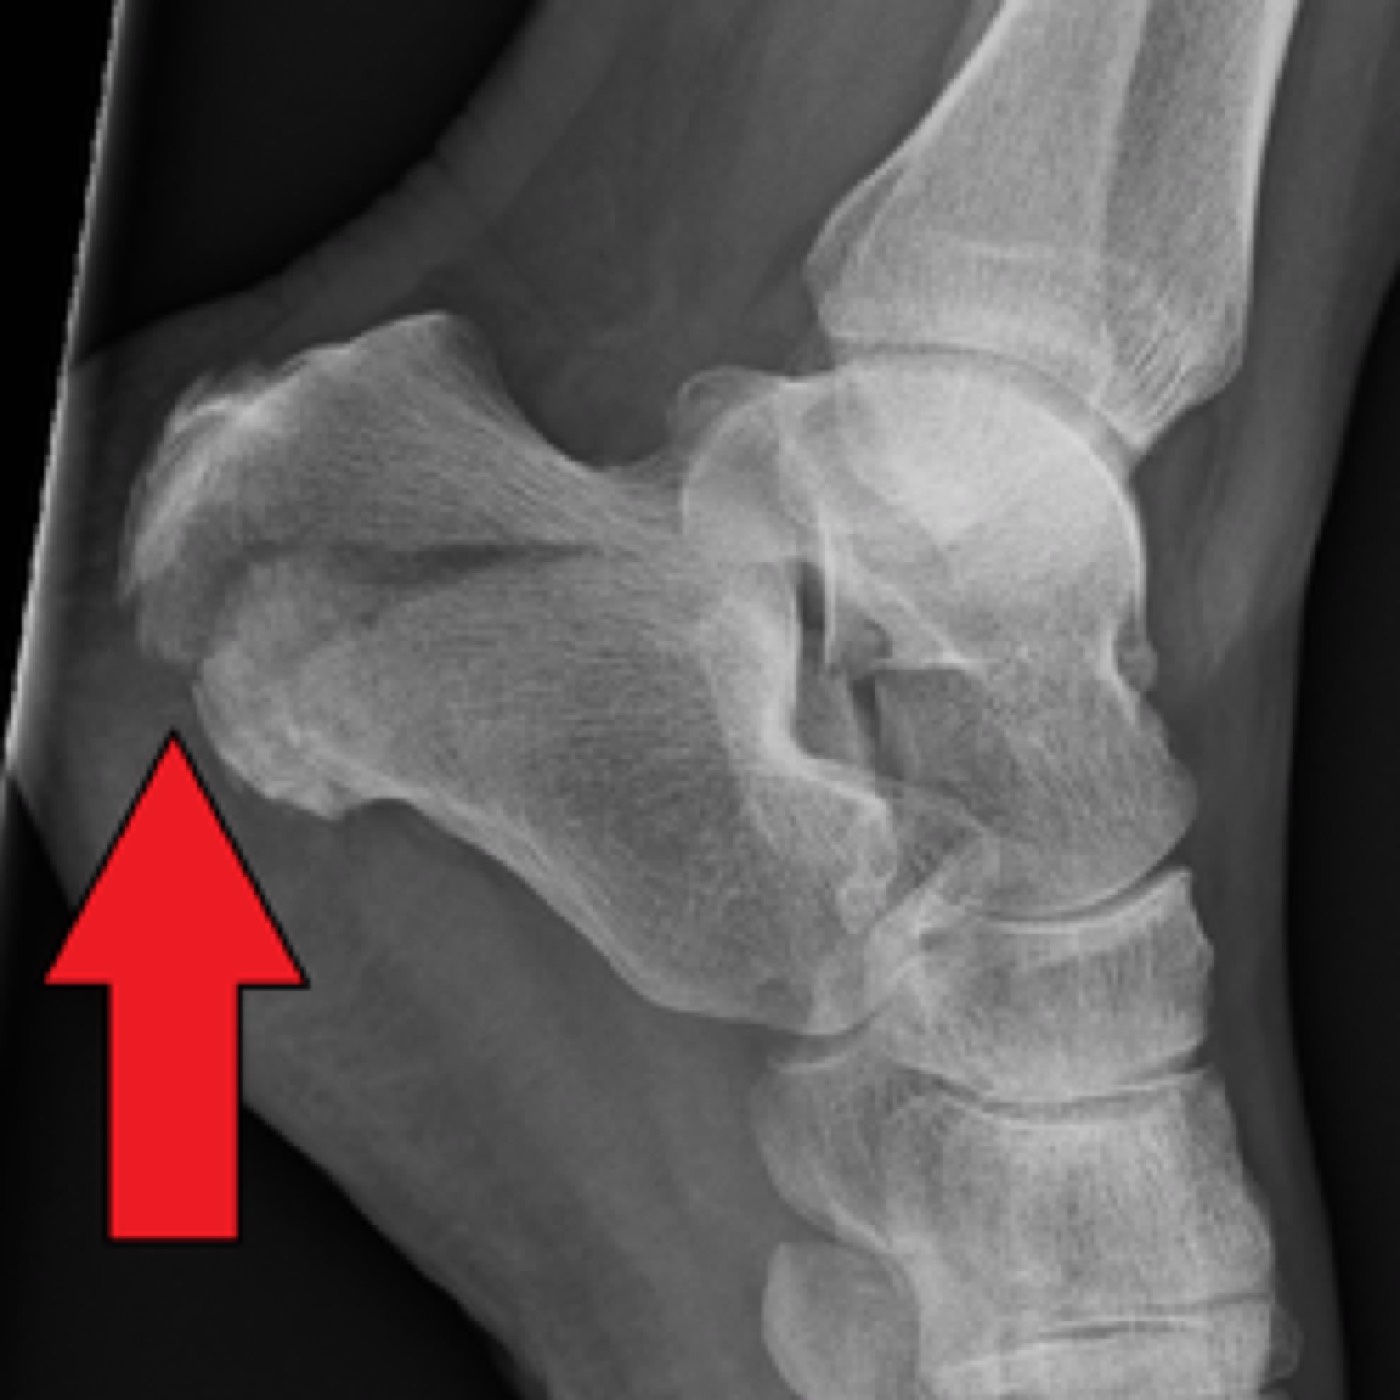

Contributors: Travis Barlock MD, Jeffrey Olson MS4 Feel free to use the cases below for your own practice. All of the scenarios are completely made up and designed to hit several teaching points. Case 1 25 M, presents to the ED with chest pain. Stabbing, started a few hours ago, substernal. Thinks it is GERD. After 2-3 minutes, pain worsens and radiates to the back. VS: BP 125/50 (Right arm 190/110). HR 120. RR of 18. Sat 98% on RA. Additional VS: Temp of 37.2, height of 6'5", BMI of 18. PMH: None, doesn't see a doctor. Meds: None FH: Weird heart thing (Mitral Valve Prolapse), weird lung thing (spontaneous pneumothorax), tall family members with long fingers and toes Physical Exam: Cards: Diastolic decrescendo at the RUSB, diminished S2. UE pulses are asymmetric, LE pulses are asymmetric, carotid pulses are asymmetric, BP is asymmetric MSK: Knees, elbows, and wrists are hypermobile. Imaging: CXR #1 normal, #2 widened mediastinum (no read yet but shows widened mediastinum), POCUS shows small effusion CTA/MRA doesn't come back until after the case. ECG: Sinus Tach Labs: NT-proBNP 500 pg/mL D-Dimer: 7000 ng/L CBC: Hemoglobin: 13.5 g/dL, WBC: 20,000/µL, Platelets: 250,000/µL Chem 7: Na 138, K, 5.7, Cl 102, Bicarb 17, BUN 45, Creatinine: 3.5 mg/dL, Glucose: 180 LFTs: Albumin 2.4, Total protein 5.5, ALP: 140, AST: 3500, ALT: 2800, TBili: 3.2, DirectBili: 2.4, Ca: 7.8 LDH: 2200 PT: 20.5, INR: 2.2, Fibrinogen: 170 5th gen High-Sensitivity Troponin: <3 Lactate: 7 mmol/L VBG: pH 7.22, paCO2 28, bicarb 15 Notes: Can have patient crash somewhere in middle and show 2nd xray Case 2: A 67-year-old female is brought to the ED by her daughter due to progressive weakness, confusion, and fatigue that have worsened over the past week. Unable to get out of bed and has become increasingly lethargic. Also having some nausea, constipation. The daughter denies any preceding illness, recent trauma, or travel. Does not know her meds but will head home to get them after talking with you. VS: BP 88/55 mmHg, HR 110, RR 20, O2 Sat 98% on room air. Additional VS: Temp 36.8°C. PMH: Hypertension, osteoarthritis, and depression. Physical exam: General: Thin, somnolent but arousable. HENT: Dry mucous membranes Neuro: Confused, A&Ox1 (self), hyporeflexia Labs (Includes many that would not return in the ED in case you want to take this case forward to the floor) CBC: WBC 9,500, Hb 16.5, Hct: 50%, Platelets 220,000 Chem7: Na 129, K 2.1, Cl 95, HCO3 34, Creatinine 1.6, BUN 40, Glucose 115 LFTs: normal Magnesium: 1.1 Calcium: 10.8 mg/dL (corrects to 12.8) iCal: 3.2 Phosphate: 2.3 mg/dL Albumin: 2 BUN:Cr ratio: 25 VBG: pH: 7.49, PaCO2 45, HCO3: 34 Lactate: 2.8 Serum Osmolality: 276 mOsm/kg (Osmolal gap of 2) Urine Osmolality: 550 mOsm/kg Urine Sodium (UNa): 10 mEq/L (low). Urine Potassium (UK): 25 mEq/L (elevated). Urine Chloride (UCl): 12 mEq/L (low). Urine Magnesium (UMg): 20 (Elevated). Urine Calcium (UCa): 50 in 24 hrs (Low) 100 cc of urine with foley FeNa Plasma renin activity: 15 mg/mL/hr (elevated), Aldosterone: 25 ng/dL (Elevated), ADH: Elevated, Diuretic screen: Positive for thiazides PTH: 8 (low), HsTrop: 32, Cortisol and ACTH: Normal. EKG: Hypokalemia features CXR: Normal Renal US: shows stones Improves with fluids Note: Can have daughter return with med list at some point including HCTZ, ibuprofen, and sertraline Case 3: Patient Presentation EMS Report: A 27-year-old male involved in a high-speed motorcycle collision is brought to the emergency department by EMS. The patient was found unconscious at the scene with evidence of severe thoracic and extremity trauma. He was intubated en route for airway protection due to altered mental status (GCS 7). VS: HR 130, BP 90/60, RR: bagging at 12 bpm, satting 88% on 100% FiO2 Primary Survey Airway: Endotracheal tube in place. Breathing: Decreased breath sounds on the left side with visible chest asymmetry and paradoxical chest wall movement. Circulation: Mottled extremities noted, with significant deformity of the right thigh. Pulses are diminished in the right leg Disability: GCS remains 7 (E1 V2 M4). Pupils equal and reactive. Exposure: Full-body examination reveals an open fracture of the right femur, multiple abrasions, and bruising over the chest wall. Vent alarms Peak Inspiratory Pressure (PIP) 40 cm H₂O (elevated) Plateau Pressure (Pplat) 35 cm H₂O (elevated) EtCO₂ (End-Tidal CO₂) 55 mmHg High-Pressure Alarm Triggering frequently Glucose 120 CBC: Hgb 8.9, Hct 27, WBC 14.2, platelets 220,000 VBG: pH 7.28, pCO2 33, bicarb 18, lactate 4.5 CXR with tension pneumothorax Patient improves after chest tube, pigtail catheter, or needle decompression. Ready to be transferred upstairs and O2 starts tanking again Vent alarms- second episode Peak Inspiratory Pressure (PIP) 35 cm H₂O (elevated) Plateau Pressure (Pplat) 30 cm H₂O (elevated) EtCO₂ (End-Tidal CO₂) 20 mmHg HR: 140, satting 84%, temp 38.5, ABG: pH 7.32, pCO₂ 30 mmHg, pO₂ 60 mmHg on 100% FiO₂, HCO₃⁻ 18 mmol/L (hypoxemia and metabolic acidosis). D-dimer: Elevated Thrombocytopenia: Platelets 90,000/µL. US shows blown right ventricle ECG shows new RBBB CT PE: Ground glass opacities, consolidation, centrilobular nodules, septal thickening, and fat-attenuating lesions. Note: Management is largely supportive care so once the diagnosis is made, end the case. References Carroll MF, Schade DS. A practical approach to hypercalcemia. Am Fam Physician. 2003 May 1;67(9):1959-66. PMID: 12751658. Coelho SG, Almeida AG. Marfan syndrome revisited: From genetics to the clinic. Rev Port Cardiol (Engl Ed). 2020 Apr;39(4):215-226. English, Portuguese. doi: 10.1016/j.repc.2019.09.008. Epub 2020 May 18. PMID: 32439107. Palmer BF. Metabolic complications associated with use of diuretics. Semin Nephrol. 2011 Nov;31(6):542-52. doi: 10.1016/j.semnephrol.2011.09.009. PMID: 22099511. Reed MJ. Diagnosis and management of acute aortic dissection in the emergency department. Br J Hosp Med (Lond). 2024 Apr 30;85(4):1-9. doi: 10.12968/hmed.2023.0366. PMID: 38708978. Roberts DJ, Leigh-Smith S, Faris PD, Blackmore C, Ball CG, Robertson HL, Dixon E, James MT, Kirkpatrick AW, Kortbeek JB, Stelfox HT. Clinical Presentation of Patients With Tension Pneumothorax: A Systematic Review. Ann Surg. 2015 Jun;261(6):1068-78. doi: 10.1097/SLA.0000000000001073. PMID: 25563887. Rothberg DL, Makarewich CA. Fat Embolism and Fat Embolism Syndrome. J Am Acad Orthop Surg. 2019 Apr 15;27(8):e346-e355. doi: 10.5435/JAAOS-D-17-00571. PMID: 30958807. Produced by Jeffrey Olson, MS4 Special thanks to Evan Fisch MD Get your tickets to Tox Talks Event, Sept 11, 2025: https://emergencymedicalminute.org/events-2/ Donate: https://emergencymedicalminute.org/donate/